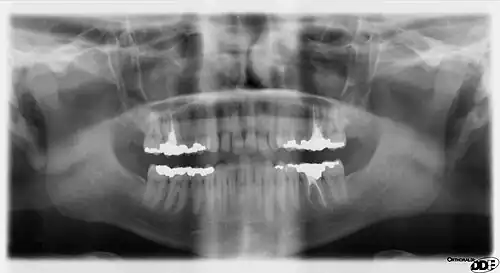

Additional images

-

Cutaway view showing spongy bone -

Turnaround with cranium -

A panoramic radiograph of the mandibular region

Rarely, a bifid IAN may be present, resulting in a second and more inferiorly placed mandibular foramen. This can be detected by noting a doubled mandibular canal via radiograph.[10]